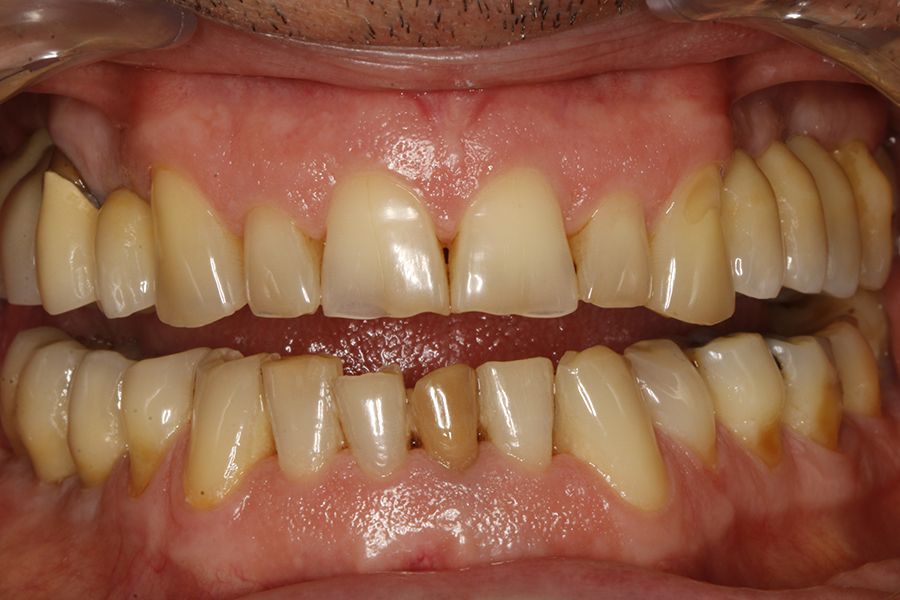

En las figuras 5-13 se muestra uno de los casos incluidos en el estudio.

En todos los pacientes se identificaron eventos adversos en sus rehabilitaciones con implantes, siendo estas complicaciones: fractura de la cerámica de la prótesis en un 63,6%, fractura estructural de la prótesis en un 18,2% de los casos (estructura en sí misma o recubrimiento de resina en las híbridas) y fracturas o fisuras en los implantes en un 18,2% de los casos. Las fracturas de las prótesis y de los implantes se vieron por igual entre hombres y mujeres, siendo la fractura de cerámica algo mayor en el grupo de los hombres (figura 1).

Conclusiones: El bruxismo y la AOS están íntimamente relacionados, así como los signos dentales de ambos procesos, como son el desgaste y la fractura de dientes, implantes o rehabilitaciones.

Conclusions: Bruxism and OSA are closely related, as are the dental signs of both processes, such as wear and fracture of teeth, implants or rehabilitations. Dentists can be a fundamental pillar in the treatment of these patients, including the first step in the diagnosis of undiagnosed cases of OSA, which can be identified through dental problems.